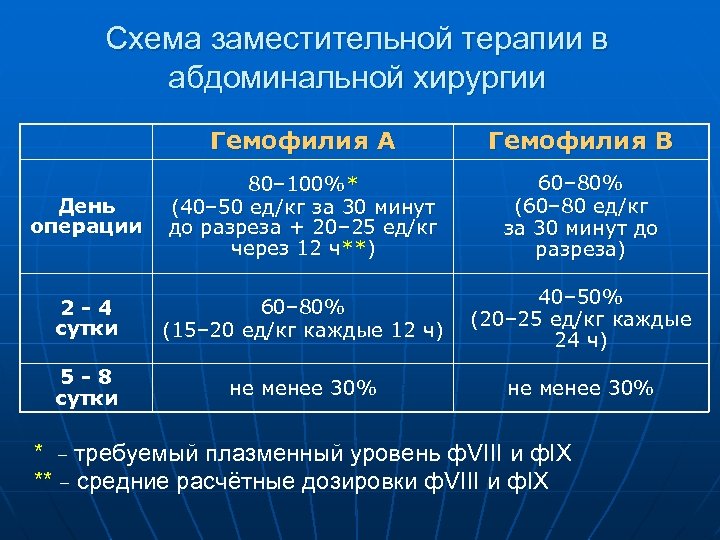

Схема заместительной терапии в абдоминальной хирургии Гемофилия А Гемофилия В День операции 80– 100%* (40– 50 ед/кг за 30 минут до разреза + 20– 25 ед/кг через 12 ч**) 60– 80% (60– 80 ед/кг за 30 минут до разреза) 2 -4 сутки 60– 80% (15– 20 ед/кг каждые 12 ч) 40– 50% (20– 25 ед/кг каждые 24 ч) 5 -8 сутки не менее 30% * – требуемый плазменный уровень ф. VIII и ф. IX ** – средние расчётные дозировки ф. VIII и ф. IX